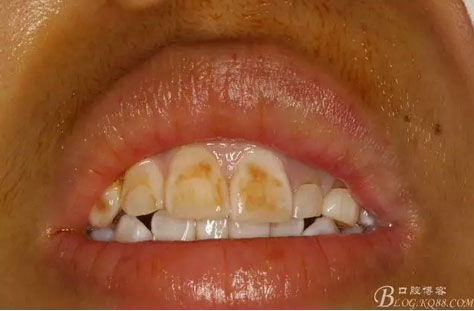

圖2.術(shù)前口內(nèi)像,左側(cè)乳Ⅱ、Ⅲ滯留,頸部楔形缺損,探針不敏感。左側(cè)乳Ⅱ、Ⅲ唇側(cè)粘膜膨隆,表面結(jié)節(jié)狀,捫診質(zhì)地堅(jiān)硬,無波動(dòng)。